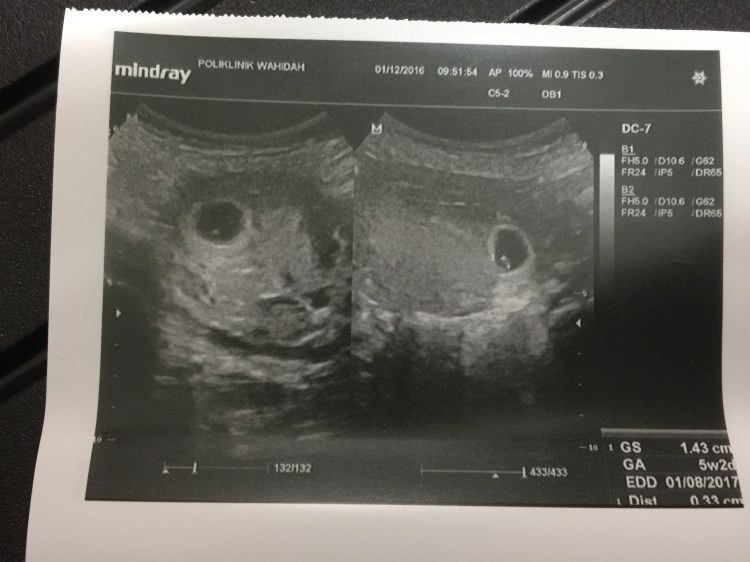

- Scan dibuat pada awalnya di Poliklinik Wahidah pada 1 December

Gambar scan pada 5 week